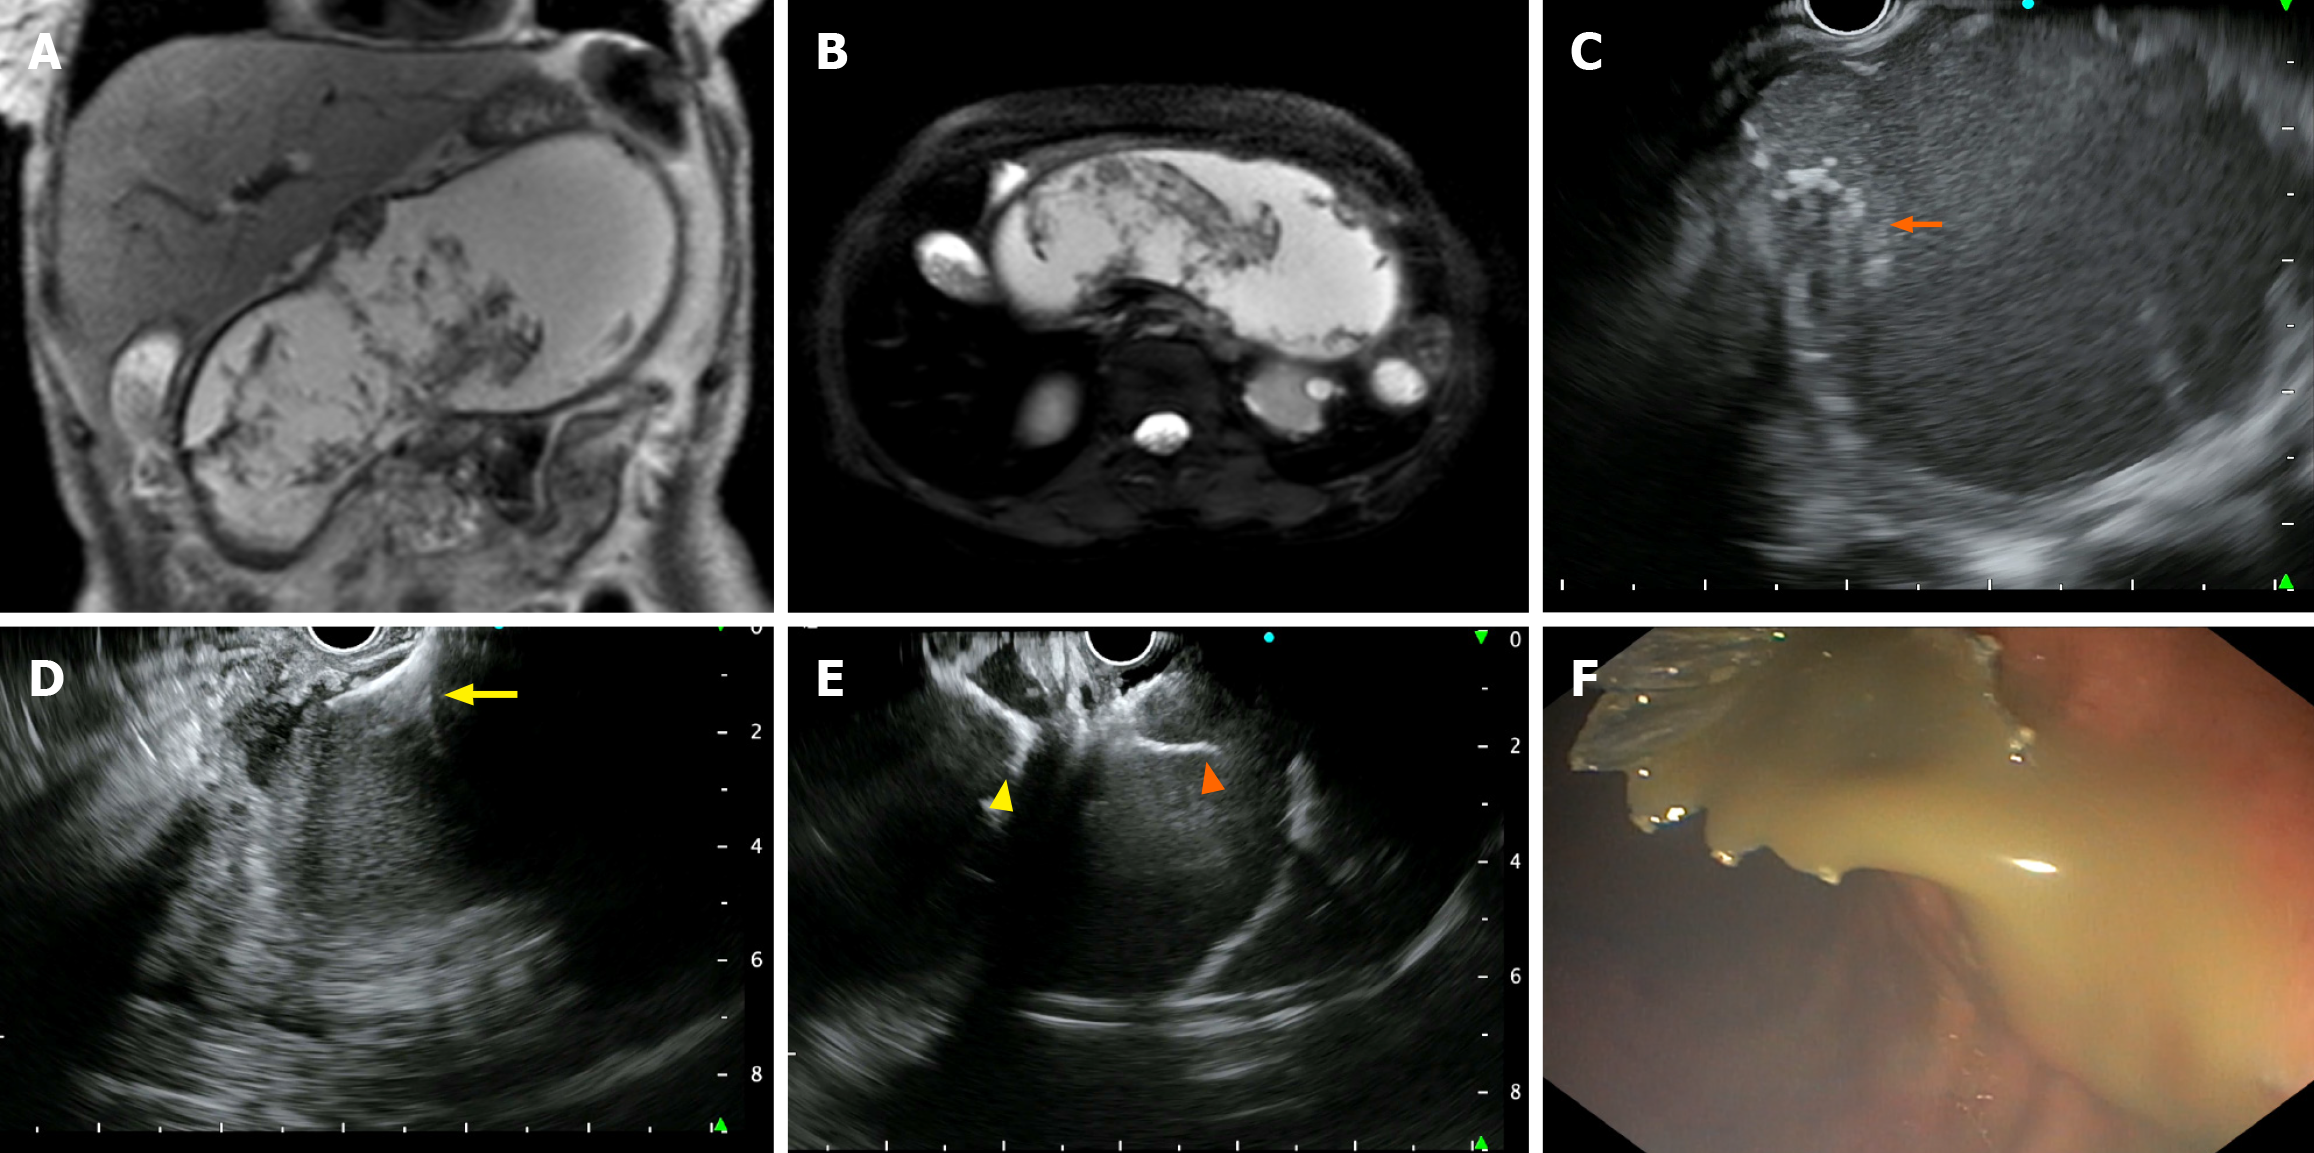

EUS-guided cystogastrostomy: An experienced therapeutic endoscopist performed all procedures using a linear echoendoscope (GF-UCT180; Olympus, Tokyo, Japan) under intravenous anesthesia. The collection was identified, and a cautery-enhanced bi-flange stent (EASE®, Scientific Healthcare, Faridabad, India) with a diameter of 16 mm and a length of 3 cm was deployed using the transgastric or transduodenal approach (Figure 1). Patients were monitored for symptom resolution and underwent repeat imaging (computed tomography or ultrasound) if symptoms persisted or at 4 weeks before stent removal. Antibiotics were administered either empirically or based on the results of microbial culture.

DEN: DEN was performed only for those who required it based on their clinical condition, such as persistent sepsis, systemic inflammatory response syndrome (SIRS), or incomplete resolution of WON. A forward-viewing endoscope (GF-UCT180; Olympus, Tokyo, Japan) was introduced into the cyst cavity through the indwelling LAMS, and the position of the metallic stent was identified. Any obstruction in the stent was cleared, and the cyst cavity was assessed for the presence of pus, debris, and the cyst wall. Snares, forceps, or baskets were used for debridement, and betadine irrigation was performed at the end of the procedure (Figure 2). The procedure was repeated only if necessary, based on the persistence of symptoms.